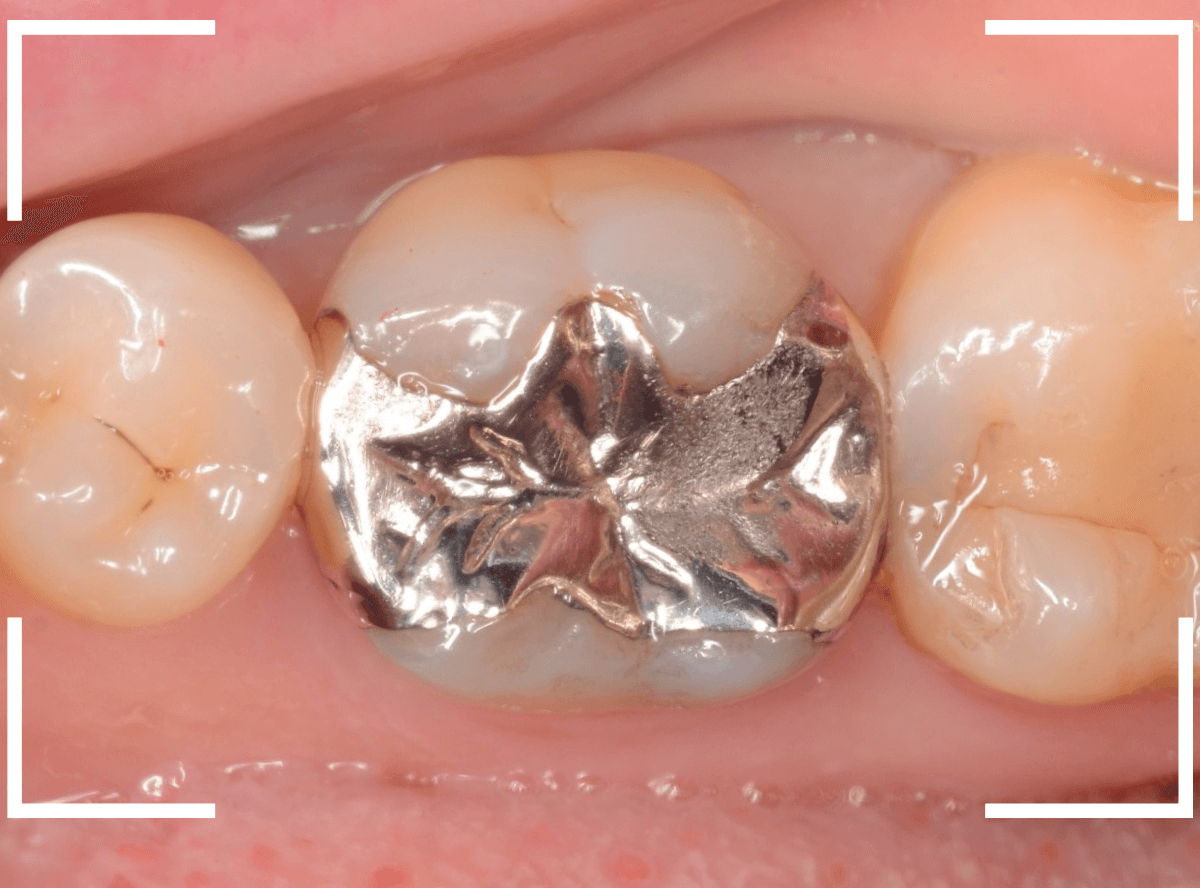

「下の奥歯の銀歯を白くしたい」というご希望の患者さんです。

メタル・インレーとメタル・クラウンが入っていますね。

検査の結果、再製に問題なさそうでしたので、治療を進める事になりました。

まずは、奥のメタル・クラウンを外します。